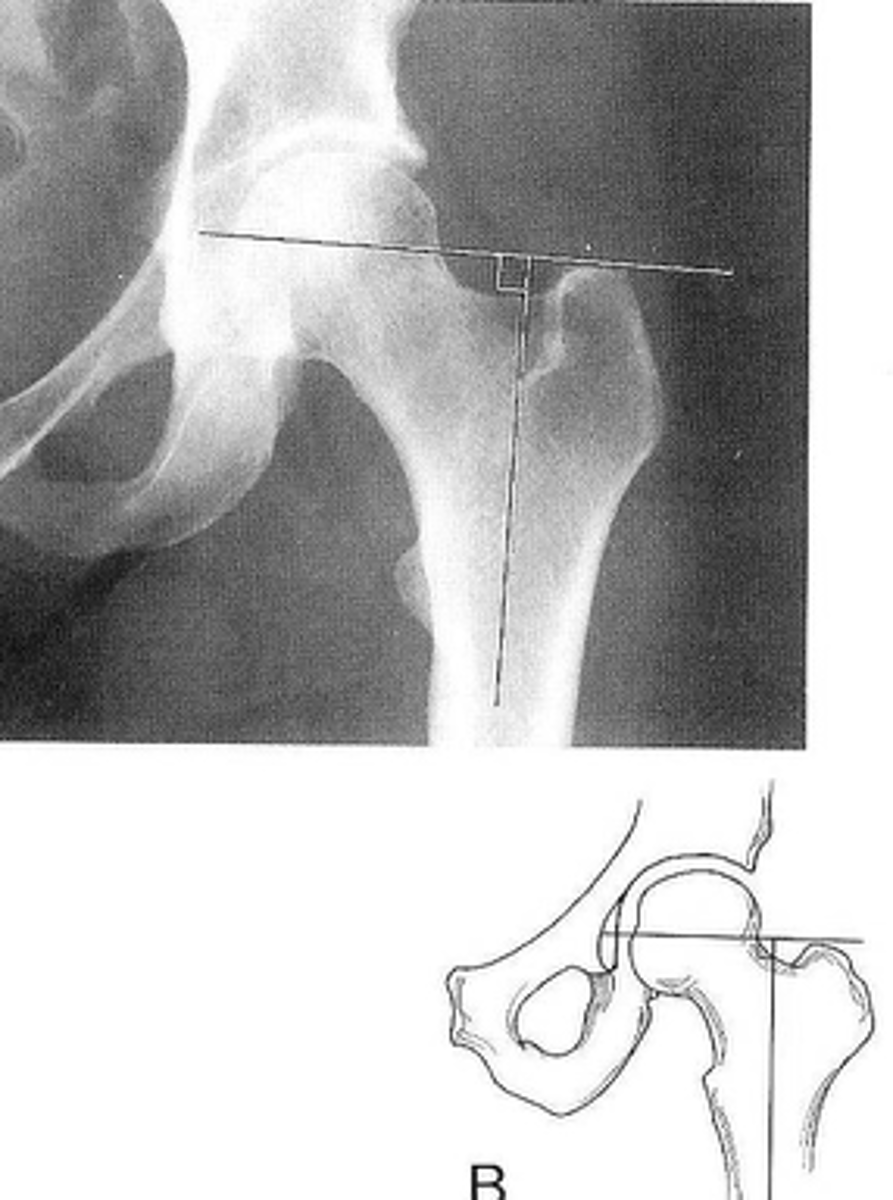

New cards

Right: gluteus medius

Left: gluteal fat stripe

ID 5

<p>ID 5</p>

10

- AP hip

- Frog-leg (lateral) hip

State the standard unilateral hip projections

11